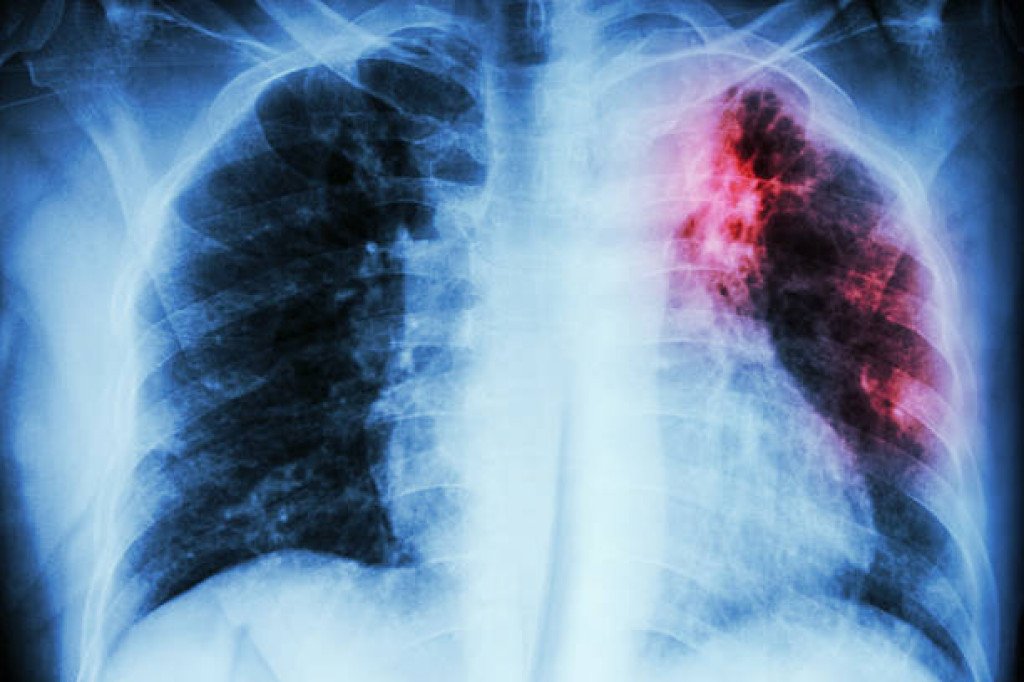

JOHANNESBURG - Juhoafrický minister zdravotníctva Joe Phaahla v nedeľu povedal, že tuberkulóza (TBC) zostáva v Juhoafrickej republike veľkou hrozbou pre verejné zdravie a za posledných pár rokov si vyžiadala viac ako 1,5 milióna životov.

"Posledných niekoľko rokov zostáva hlavnou príčinou úmrtí v krajine. Zahŕňa tiež viac ako polovicu úmrtí medzi ľuďmi nakazenými vírusom HIV, čo predstavuje 53 percent," povedal Phaahla počas pripomenutia si Svetového dňa tuberkulózy, ktorá pripadla na nedeľu.

Očakáva sa, že počet prípadov TBC v roku 2022 klesne na 280 000 zo 644 000 v roku 2007, uviedol minister a dodal, že úmrtia súvisiace s TBC tiež klesajú, ale oveľa pomalšie.